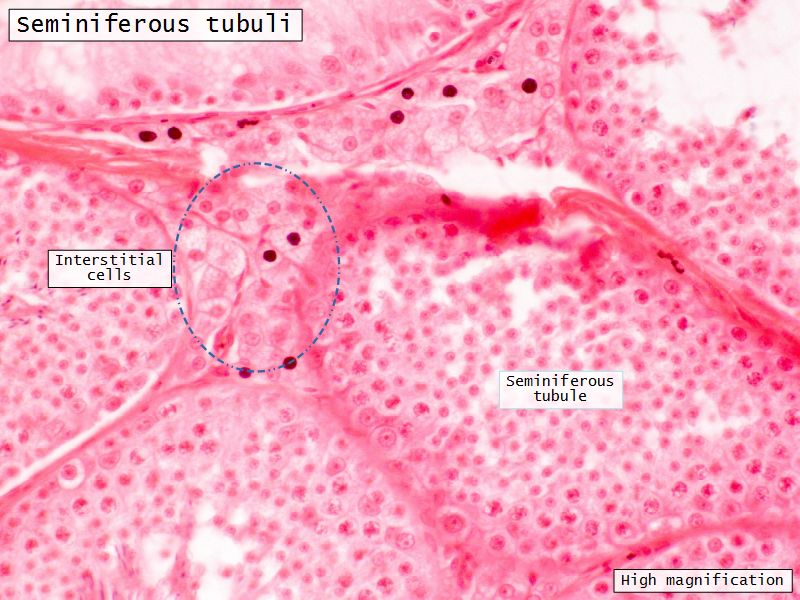

- Leydig cells

Leydig cells

- Interstitial cells

- Surrounded by rich AVL

- Large round - polygonal shape with clear cytoplasm

- Large central nucleus

- Endocrine - testosterone

Seminiferous tubuli

- Site of spermatozoa production